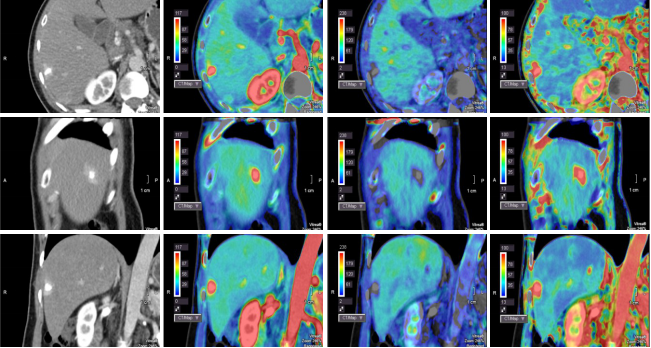

病例一 34歲, 男, 右肝血管瘤。

灌注檢查可見(jiàn)肝臟內(nèi)一類圓形病灶,AF為血流高灌注,PF為血流低灌注。

可以自動(dòng)一鍵提取肝動(dòng)脈、 門靜脈以及腫瘤, 并且進(jìn)行融合, 觀察腫瘤與動(dòng)脈及門脈血管的關(guān)系。

640層寬體探測(cè)器CT對(duì)于肝臟全器官灌注掃描,不但能夠精確顯示動(dòng)脈期、門脈期、靜脈期的3D解剖結(jié)構(gòu),而且可以同時(shí)探查腫瘤的供血?jiǎng)用}、流出靜脈,分析肝實(shí)質(zhì)的血供和灌注情況。所有這些檢查都以極低的劑量在一次檢查中完成,對(duì)肝腫瘤的診斷與治療及效果評(píng)估具有重大意義。除此之外,特有的肝血管融合技術(shù),可用于肝臟手術(shù)模擬以及肝臟腫瘤的分割和量化。